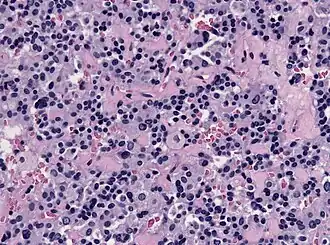

This image shows the histology of a thyrotroph tumor. These thyrotroph tumors are referred to as thyrotroph adenomas, and are very rare. They typically present as functional macroadenomas and generally appear in individuals in their 50s. Thyrotroph adenomas are not well understood as they only comprise roughly 1% of all pituitary tumors.[9] These tumors typically result in increased secretion of TSH. Individuals with thyrotroph adenomas typically have hyperthyroidism and diffuse goitre. Diffuse goitre refers to the elongated enlargement of the thyroid gland that results from the increased expression of TSH.[10]

In histological staining, the thyrotropic cells appear more elongated and spindle shaped and are regularly accompanied by fibrosis.[9]